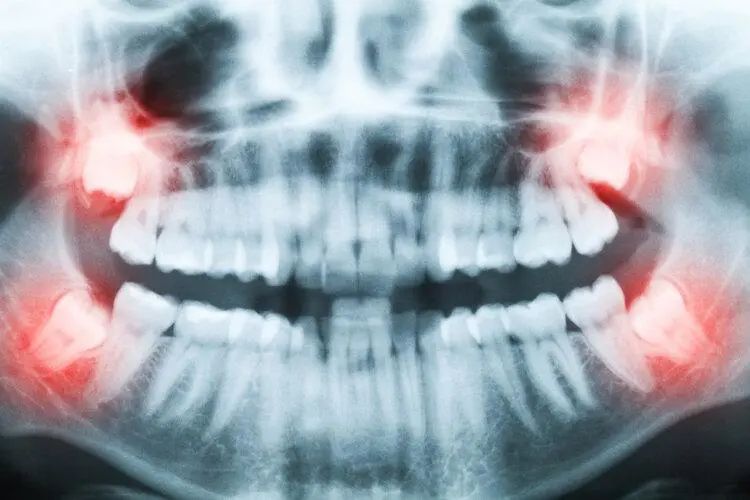

3、智齿

不少人被智齿折磨过,正常情况下,我们在12岁之前会完成换牙。但是在16~25岁左右,智齿开始萌出,它没有任何功能,只是人类进化遗留的产物,还容易导致异位生长、阻生,引发牙龈红肿、牙周炎等口腔疾病。